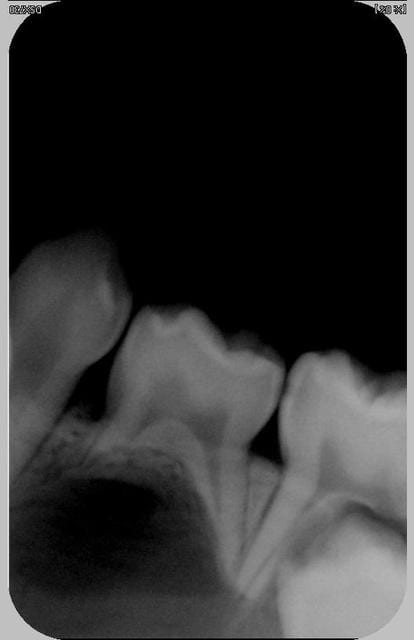

J'ai extrait la 74.

Elle était vivante, saine autant que je puissen en juger. Un surface osseuse nette et en bonne état était présente sous la dent.

A l'ouverture, la paroi kystique était épaisse et peu adhérente. Je n'ai pas pris le risque de tirer dessus, je l'ai vidé gentillement et suturé surtout pour limiter l'alimentation alimentaire de la cavité.

Ah j'oubliais! en curetant en périphérie de la 74 pas de sensation de racine de 73 et 75 proéminente...